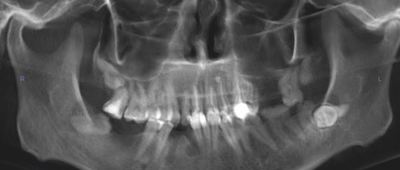

А для того, что ортопантомография (ОПТГ, обзорный или панорамный снимок зубов), является плоскостным, а значит происходит наложение каждой детали снимка послойно друг на друга. Следовательно, рассмотреть объект исследования, в частности, область зуба мудрости, расположенного рядом нижнечелюстного нерва, во всех плоскостях, под иным углом или другой проекции невозможно. КЛКТ (Конусно-лучевая компьютерная томография), напротив дает нам такую возможность.